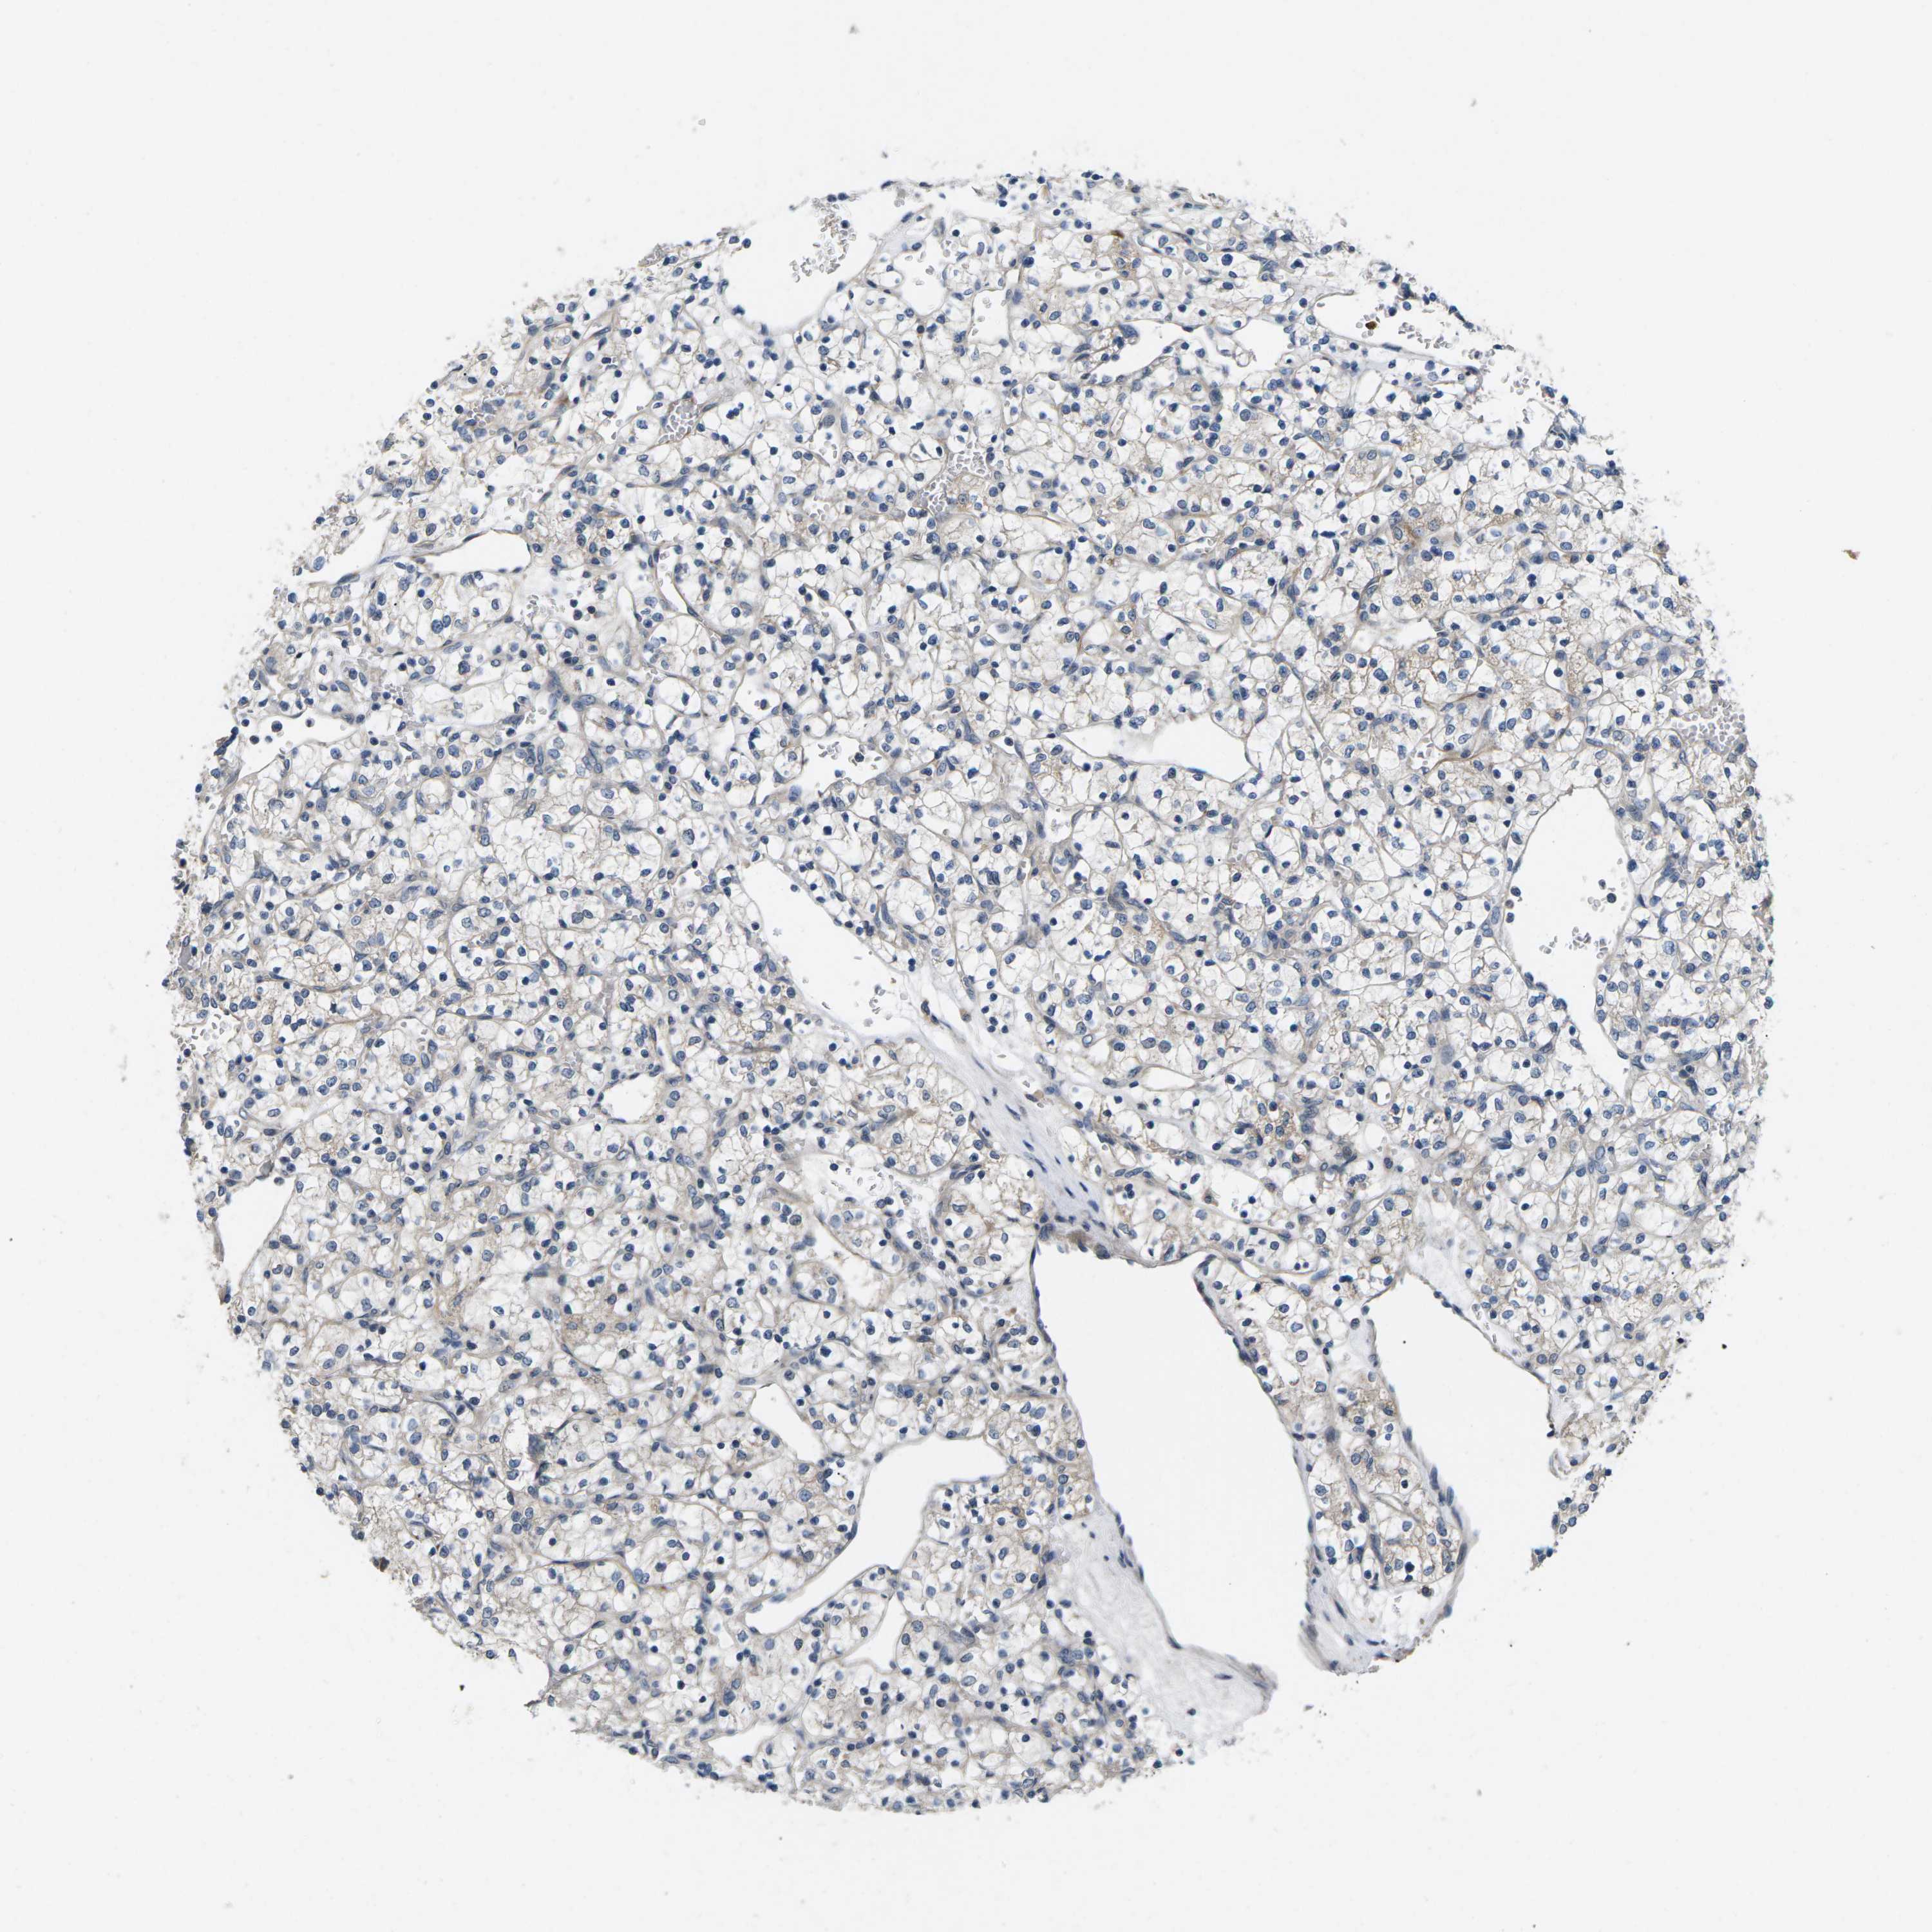

CANCER RENAL CANCER Show tissue menu

KICH TCGA KIRC TCGA KIRC VALIDATION KIRP TCGA PROTEIN RCC CPTAC PROTEIN EXPRESSION